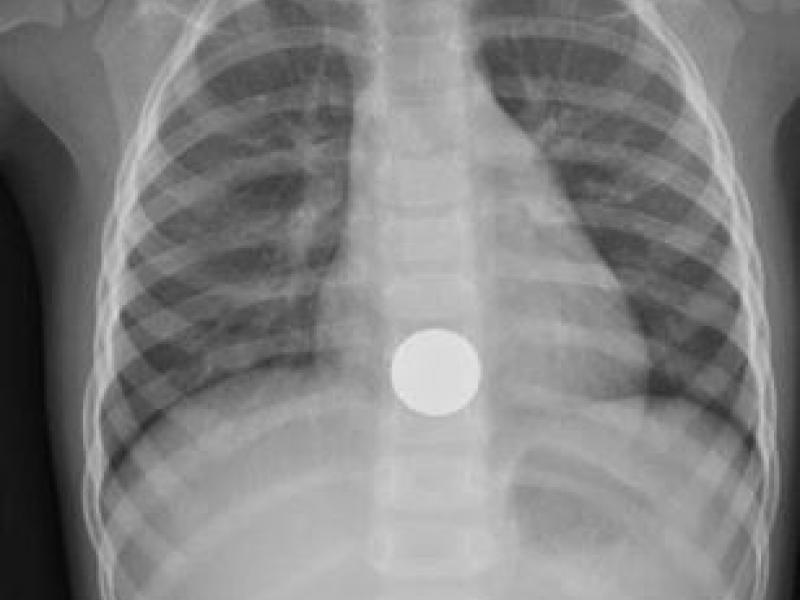

A 2 year old F presents to the ED with her parents with